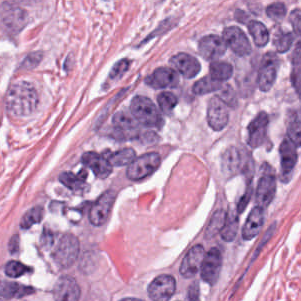

As an essential part of digital pathology, histopathology image analysis is playing increasingly important role in cancer diagnosis, which can provide direct and reliable evidence to diagnose the grade and type of cancer. This paper deals with nuclei segmentation, an important step in histopathological image analysis. The purpose of nuclei semgentation is not only counting the number of nuclei but also obtaining the detailed information of each nucleus. So unlike nuclei detection, here the outputs are the contour of each nucleus instead of only the position of their central points. Hence we can exactly extract each nucleus from the image and make it available for further analysis. For example, the features of the individual nucleus and the distribution of nuclei clusters can be used to grade and classify status of breast cancers [3, 4]. Because of appearance variation such as color, shape, and texture, nuclei segmentation from histopathological images could be very challenging, as illustrated in Fig.1, in which it is very challenging even for human to recognize and segment all nuclei within the images. Fig.1(a) and Fig.1(b) illustrate two histopathological images from different organs. Fig.1(c) and Fig.1(d) are two histopathological images from same organ but have different cancer grade.

H&E stain is the most widely used stain protocol in medical diagnosis. Typically, the nuclei of cells are stained to blue by Haematoxylin while cytoplasm is colored to pink by Eosin. But in practice, the color of H&E stained images could vary a lot due to variation in the H&E reagents, staining process, scanner and the specialist who performs the staining, as shown in Fig.1. A few H&E stain normalization methods[23, 24, 25] have been proposed to eliminate the negative interference caused by color variation. We tried two of them[23, 25] to normalize the raw H&E stained images. For our segmentation algorithm, we did not find any considerable difference between these two normalization methods. Particularly, the result shown in experiment section III is generated based on the images normalized by the method in [23]. Given a target image, this method is able to convert one image’s color into the target image’s color space based on sparse non-negative matrix factorization(NMF). We choose one best stained H&E image as the target and convert other images into its color space. According to the recommendation in [23], the hyper-parameter should be set between 0.01 and 0.1. In our experiment, is set to 0.1.

Figure 6 shows how our method segments the nuclei step by step. The color variety is well controlled by the color normalization procedure. The prediction result shows clear nuclear areas and nucleus boundaries. In the final segmentation result and ground truth image, each nucleus is represented by a different color.